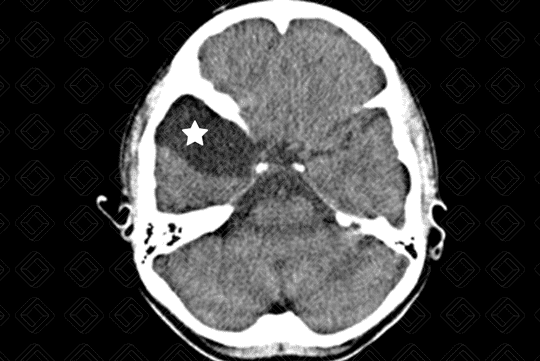

Descrição da lesão: Tomografia computadorizada do crânio. Lesão hipodensa, extra-axial, com densidade semelhante ao liquor, na fossa craniana média, deslocando o lobo temporal direito posteriormente (asterisco).

Cisto aracnoide: Caracteriza-se por uma expansão meníngea, em forma de bolsa, preenchida por líquido, com densidade semelhante ao liquor, mais comumente diagnosticada nas crianças e adultos jovens, sendo frequentemente um achado de imagem. Sua localização mais comum é na fossa craniana média (50-60% dos casos), mais especificamente na região temporal, adjacente à fissura sylviana. Outras localizações menos comuns são ângulo pontocerebelar e suprasselar (10% cada).

• Tomografia computadorizada do crânio: Lesão extra-axial, hipodensa, com densidade semelhante ao liquor e sem realce pelo meio de contraste. Pode ocorrer remodelamento ósseo da calota craniana adjacente à lesão, especialmente na população pediátrica;